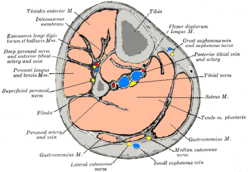

Cross-section through middle of leg. (Extensores longi digitorum et hallucis labeled at upper left.) | |

The Extensor hallucis longus is a thin muscle, situated between the Tibialis anterior and the Extensor digitorum longus, that functions to extend the big toe and dorsiflex the foot, and assists with foot eversion and inversion.

It arises from the anterior surface of the fibula for about the middle two-fourths of its extent, medial to the origin of the Extensor digitorum longus; it also arises from the interosseous membrane to a similar extent.

The anterior tibial vessels and deep peroneal nerve lie between it and the Tibialis anterior.